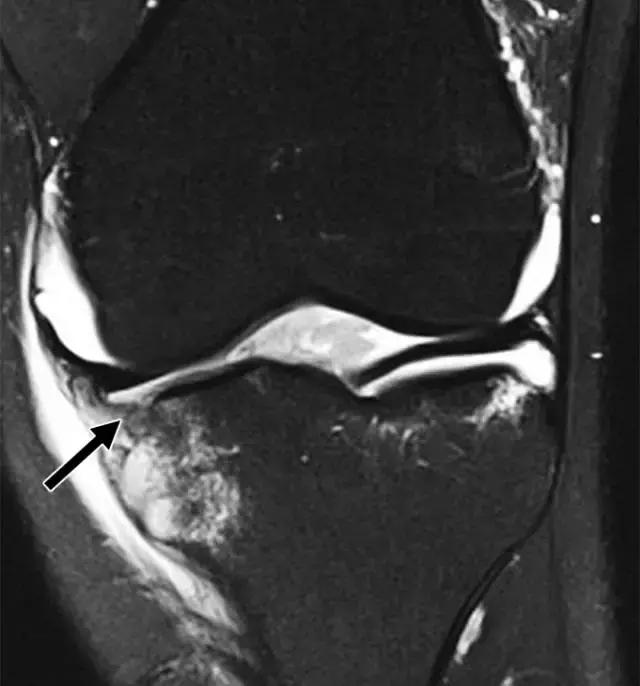

反向Segond骨折,是内侧胫骨平台的撕脱骨折,它是后交叉韧带严重受损的标志。这种骨折中的放射学检查结果与经典Segond骨折相似,只是反向骨折涉及胫骨近端的内侧(图6A)。据认为是由于内侧副韧带的深部荚膜组分的撕脱引起的(图6B),并且经常与内侧副韧带的严重损伤和相邻内侧半月板的周边损伤有关。

图6A -18岁的女性患有反Segond骨折。膝盖倾斜放射照片显示沿内侧胫骨平台的小撕裂性骨折(箭头)。

图6B,冠状脂肪抑制T2加权MR图像显示内侧胫骨平台内有明显的骨髓水肿,与内侧副韧带深部囊膜组分相关的反向Segond撕脱性骨折(箭头)。